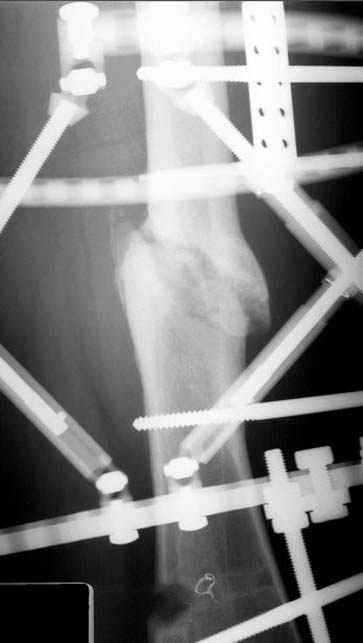

Несколько снимков из моей коллекции, чтобы разьяснить, почему мы до сих пор делаем различные варианты остеотомии.

N3 рисунок окончательный снимок, после операции моя рентгенограмма должен выглядеть примерно как эта картина. На N4 снимке клин перед удалением; N5 послеоперации 3 нед.; N6 окончательная рентгенограмма.

Отправитель: Djoldas Kuldjanov 23 Ноябрь 2004, 18:21

пластическая модель; и коррекция бедра аппаратом Илизарова.

хотя даже если бы и инфекция , то nail exchange с рассверливанием канала - вариант дебрайдмента) Я думаю, что последовательность развития событий:

Узкий к-м канал - тонкий гвоздь- усталостный перелом дистальных винтов - развитие нестабильности и как ее результат остеолиз вокруг гвоздя - деформация анатомической оси бедра. Похоже, что я понял почему аппарат, а не новый гвоздь:-)